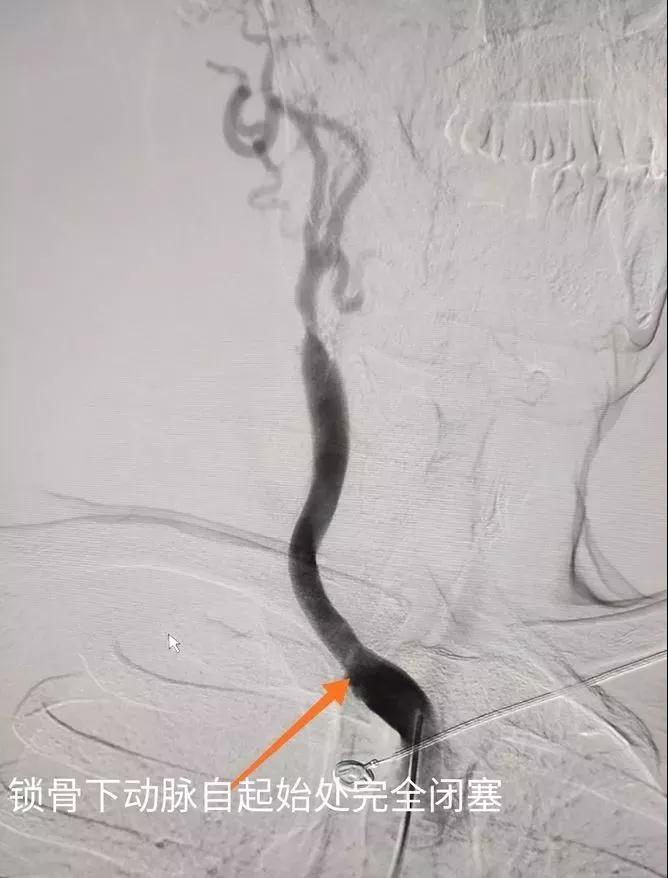

患者行腦血管造影后,發(fā)現(xiàn)右鎖骨下動脈慢性完全閉塞,右頸內動脈完全閉塞,右頸外動脈及左椎動脈代償右椎動脈血流,右頸內動脈血流緊靠左椎動脈部分代償供血。如不及時開通右鎖骨下動脈,患者腦供血無法改善,有造成偏癱及昏迷風險!

與患者家屬充分溝通后,我們決定給患者開展鎖骨下動脈再通手術。常規(guī)右側股動脈穿刺入路開通,但是由于右鎖骨下動脈開口處完全閉塞!怎么辦?有人提出放棄治療?